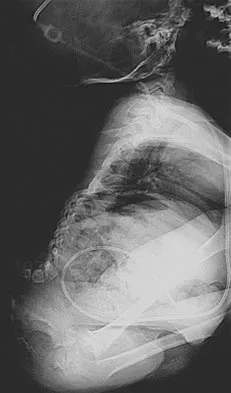

Question 38High Yield

Figure 11a shows the clinical photograph of a 46-year old woman who reports a 3-week history of pain and a "lump" at the base of her neck. She is otherwise in good health and denies any trauma. A 3-D reconstruction CT is shown in Figure 11b. What is the most likely diagnosis?

Explanation